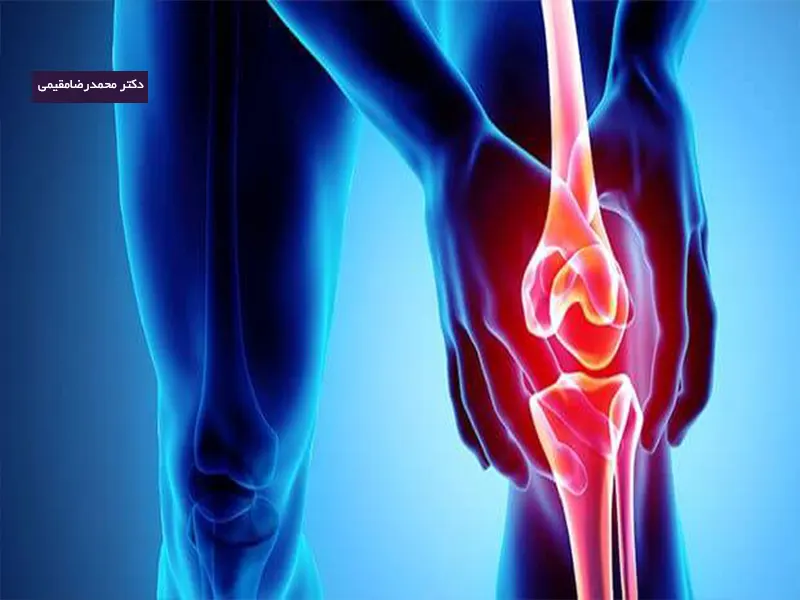

آرتروز یک بیماری التهابی در داخل و اطراف مفاصل است که افراد مختلف در سنین و شرایط مختلف را درگیر میکند. این بیماری دردناک است و باعث از دست دادن نیروی کار و ناتوانی می شود. آرتروز سالهاست که به عنوان یک بیماری پیری طبیعی و فرسودگی پذیرفته شده است. تغییرات پاتولوژیک رایج در آرتروز به ویژه در مفصل، استخوان زیر غضروفی، مایع مفصلی و کپسول تشخیص داده می شود. این بیماری امروزه دارای درمان های مختلف و موثری بوده و می توان به خوبی از دردها و عوارض آن رهایی پیدا کرد. با ما تا انتهای مقاله همراه باشید تا بیشتر در این مورد بدانید.

مفاصل و عضلات بدن در معرض آسیب و ضربه قرار دارند. در بسیاری از موارد، خود بدن قادر به ترمیم و جبرانآسیب است. اما در صورت بروز آرتروز، غضروف پوشش دهنده استخوان ها به تدریج تحلیل می رود و منجر به بروز درد، تورم و مشکلات حرکتی در مفاصل خواهد شد. علت اصلی بروز آرتروز به طور قطعی مشخص نیست، اما برخی عوامل احتمال ابتلا به این اختلال را افزایش می دهند، که عبارتند از:

آرتروز یا همان استئوآرتریت، اختلالی است که با درد و سفتی مفاصل همراه بوده و یکی از شایع ترین انواع آرتریت است. بیشتر افراد مبتلا به آرتروز، از درد مفاصل و برخی دیگر نیز از تورم و یا شنیده شدن صدا از مفصل درگیر شکایت میکنند. در برخی موارد شدت علائم خفیف بوده و تنها بعضی مواقع در فرد ظاهر می شود. اما این درد می تواند ادامه دار شود و شدت درد به حدی برسد که فرد قادر به انجام کارها و فعالیت های روزانه خود نباشد. آرتروز عمدتا در نواحی مانند زانو، مفصل ران و دست ها مشاهده می شود. در صورت ادامه دار شدن علائم توصیه می شود به متخصص ارتوپد در تهران مراجعه کنید.